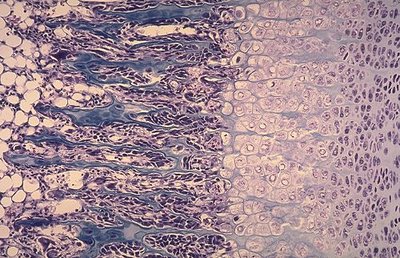

--> Les chondrocytes s'empilent et forment des "colonnes de groupes isogéniques" de manière à constituer un "cartilage de type sérié".

Mais j'ai remarqué que ça ressemble à la croissance interstitielle du cartilage quand les chondrocytes s'alignent en colonnes et formes des groupes isogéniques axiaux.